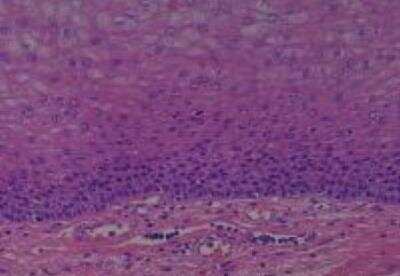

Hematoxylin & Eosin Stain: Human Common Tissue MicroArray (Normal Adjacent) [NBP2-30215] - 01. Stomach